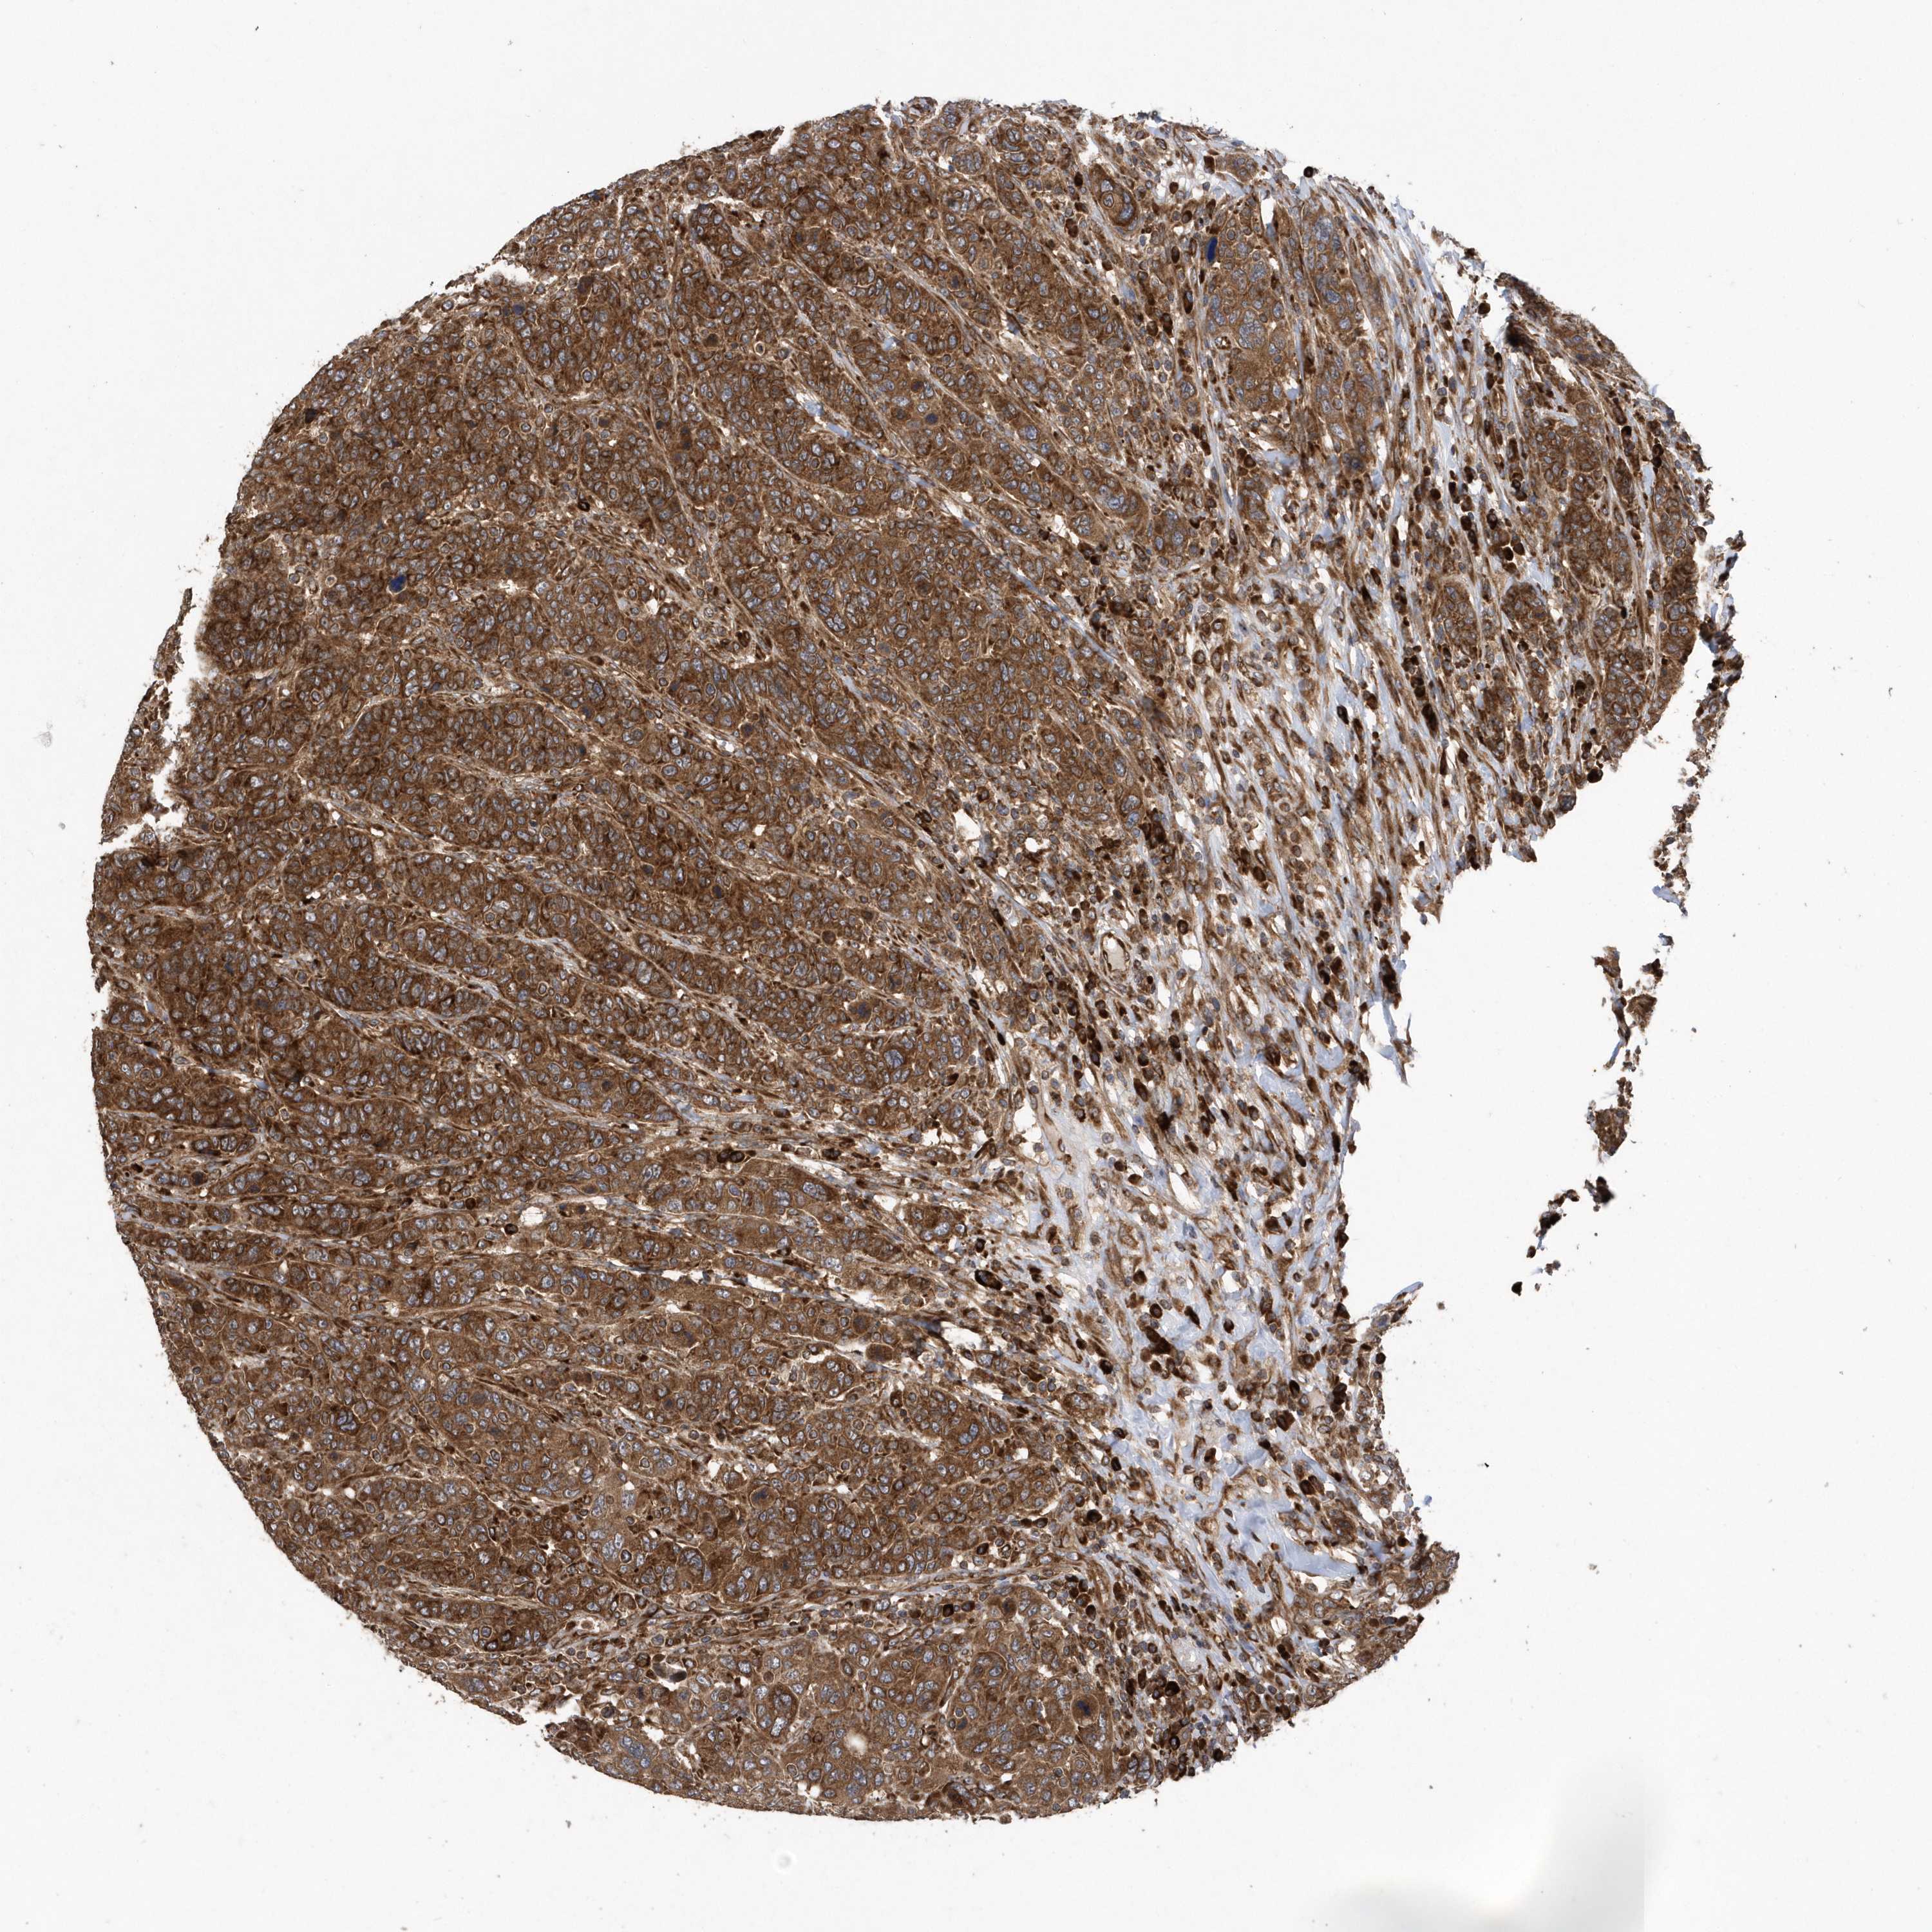

CANCER BREAST CANCER Show tissue menu

BRCA TCGA BRCA VALIDATION PROTEIN EXPRESSION